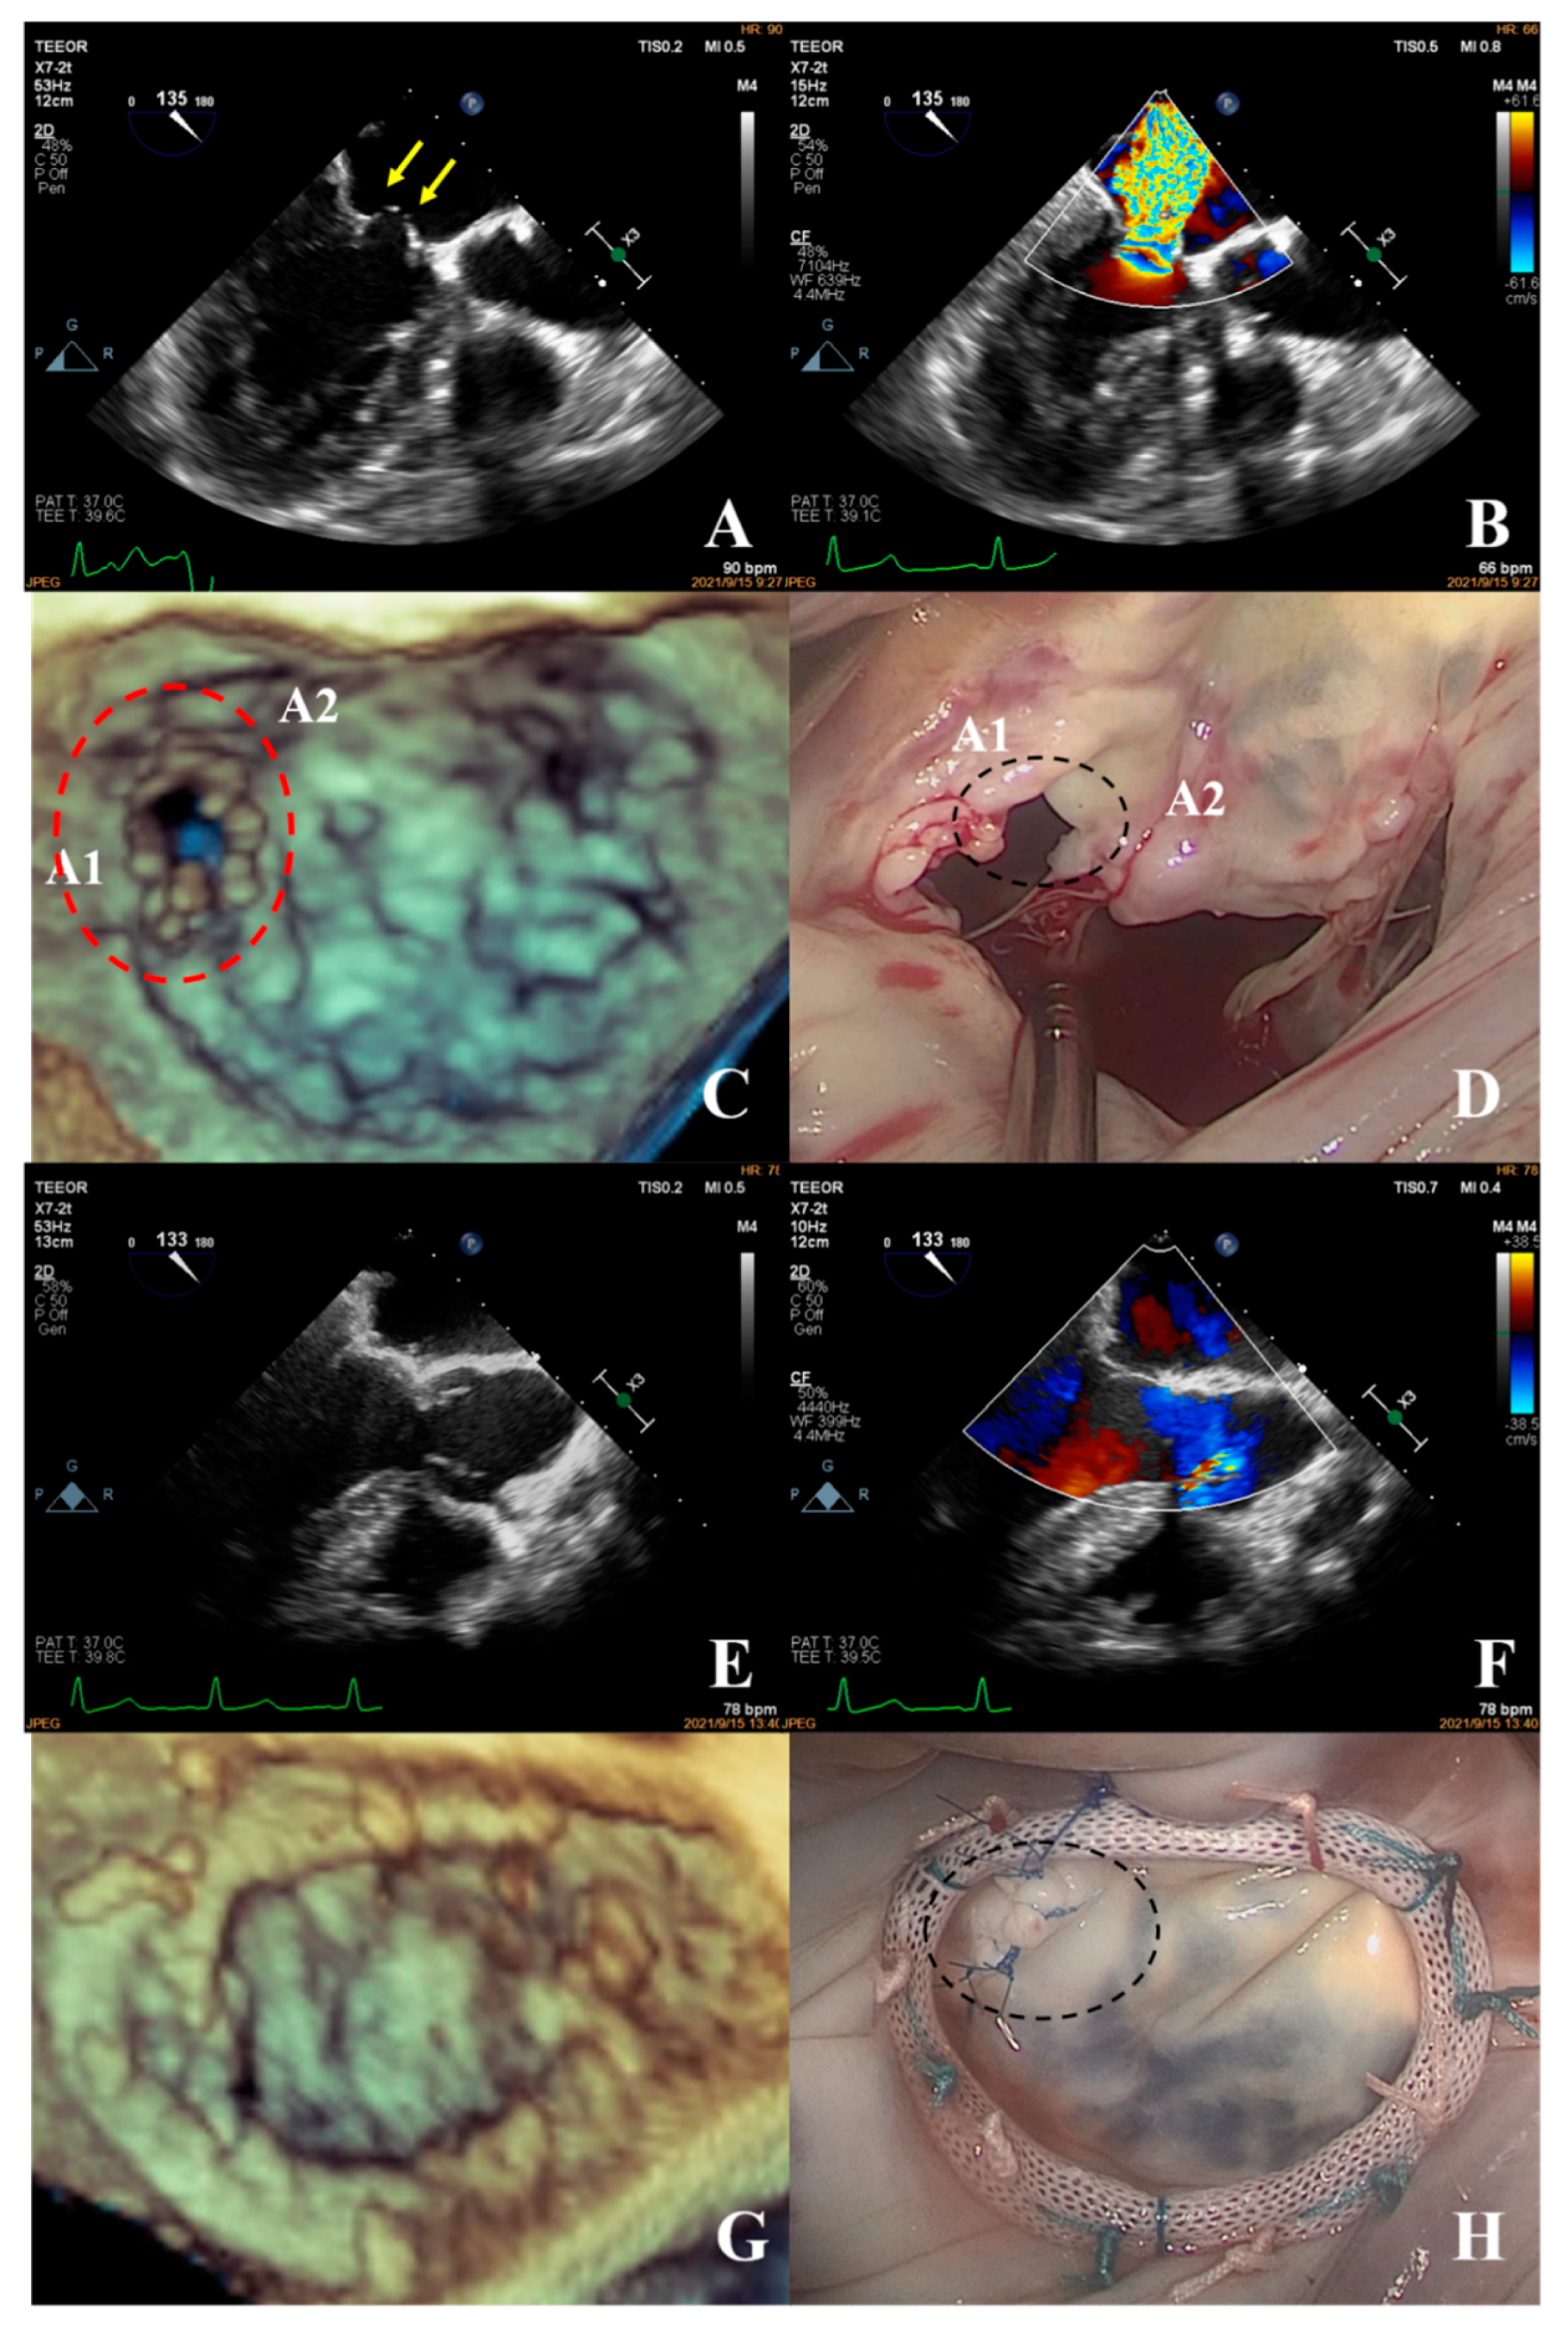

- In the simple group, the etiology was primarily secondary annular enlargement or mitral valve prolapse in an isolated segment leading to mitral regurgitation. The most commonly used technique was annuloplasty. The coaptation area of the valve leaflets was increased to reduce or even eliminate mitral regurgitation. For example, the complexity score was 3 (2 + 1) for a patient with A1 segment prolapses, a mitral anterior leaflet cleft, no chordae tendineae rupture, and no leaflet calcification, which classified the patient in the simple group. The cleft was sutured during the operation and a mitral annuloplasty ring was placed. The surgical technique score was 2 (1 + 1). After resuscitation, the surgical effect was good and no obvious regurgitation signal was observed (Figure 7).